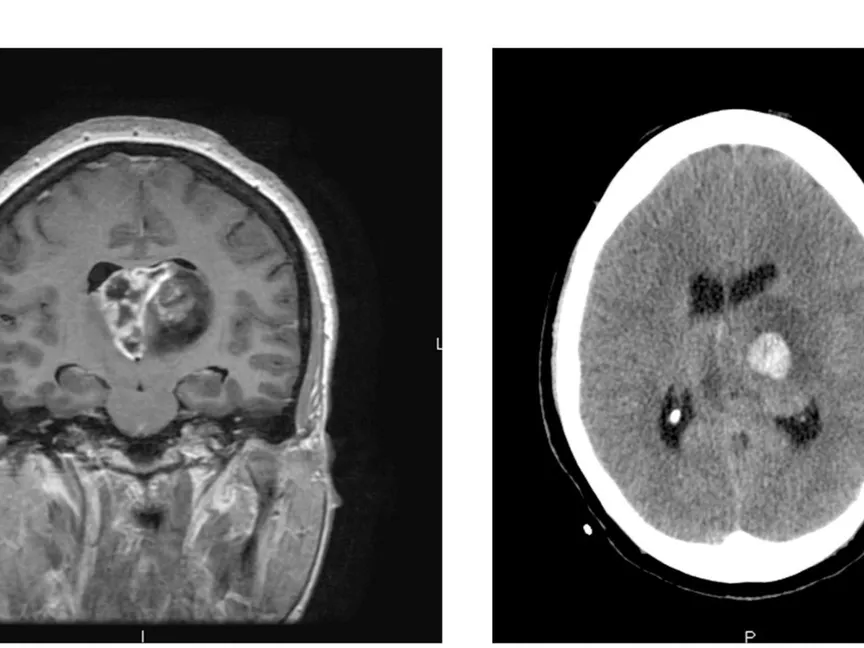

ما هو الورم الأرومي الدبقي؟

- نوع من السرطان يبدأ في الدماغ أو الحبل النخاعي.

- يتكون من خلايا تُسمى "الخلايا النجمية" التي تدعم الخلايا العصبية.

- ينمو بسرعة وقد يغزو الأنسجة السليمة ويدمرها.

- يمكن أن يصيب أي عمر، لكنه أكثر شيوعًا لدى البالغين الأكبر سنًا.

- لا يوجد علاج شافٍ حتى الآن، لكن العلاجات تساعد على إبطاء النمو وتخفيف الأعراض.